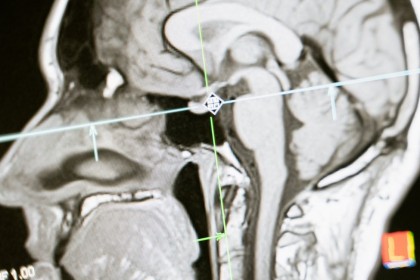

Radițiile utilizate în medicină sunt cunoscute sub denumirea de radiații ionizante. Potrivit studiilor realizate de Harvard Medical School și Organizația Mondială a Sănătății (OMS), radiațiile ionizante sunt folosite în radiografii și radioterapie, deoarece au suficientă energie pentru a modifica ADN-ul celular.În cazul radiografiilor, aceste radiații sunt utilizate pentru a obține imagini clare ale structurilor interne ale corpului, care sunt esențiale în diagnosticarea diferitelor afecțiuni. Imaginile permit medicilor să identifice problemele de sănătate și să stabilească un tratament adecvat. În radioterapia pentru cancer, radiațiile ionizante sunt utilizate pentru a distruge celulele tumorale. Ele sunt direcționate cu precizie către tumora afectată, având scopul de a reduce dimensiunea acesteia și de a opri creșterea celulelor canceroase. Metoda este esențială în lupta împotriva cancerului, contribuind semnificativ la îmbunătățirea șanselor de recuperare a pacienților. Când sunt utilizate corect și sub supraveghere medicală, radiațiile ionizante pot salva vieți, iar tehnologiile moderne permit reducerea riscurilor pentru pacienți.

Potrivit Organizației Mondiale a Sănătății (OMS), radiațiile medicale sunt reglementate riguros, iar expunerea este controlată pentru a reduce orice pericole. În comparație cu avantajele semnificative, cum ar fi diagnosticarea precisă și tratamentele eficiente care pot salva vieți, riscurile asociate cu radiațiile medicale sunt nesemnificative.

De asemenea, pentru investigațiile medicale, OMS sugerează consultarea medicului despre alternativele care implică expunerea mai redusă la radiații, cum ar fi ecografiile, în locul radiografiilor sau tomografiilor atunci când este posibil.